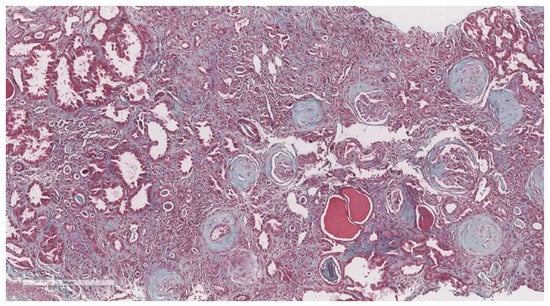

2.3. Renal Biopsy and Histopathology

- Haas, M.; Seshan, S.V.; Barisoni, L.; Amann, K.; Bajema, I.M.; Becker, J.U.; Joh, K.; Ljubanovic, D.; Roberts, I.S.; Roelofs, J.J.; et al. Consensus definitions for glomerular lesions by light and electron microscopy: Recommendations from a working group of the Renal Pathology Society. Kidney Int. 2020, 98, 1120–1134. [Google Scholar] [CrossRef]